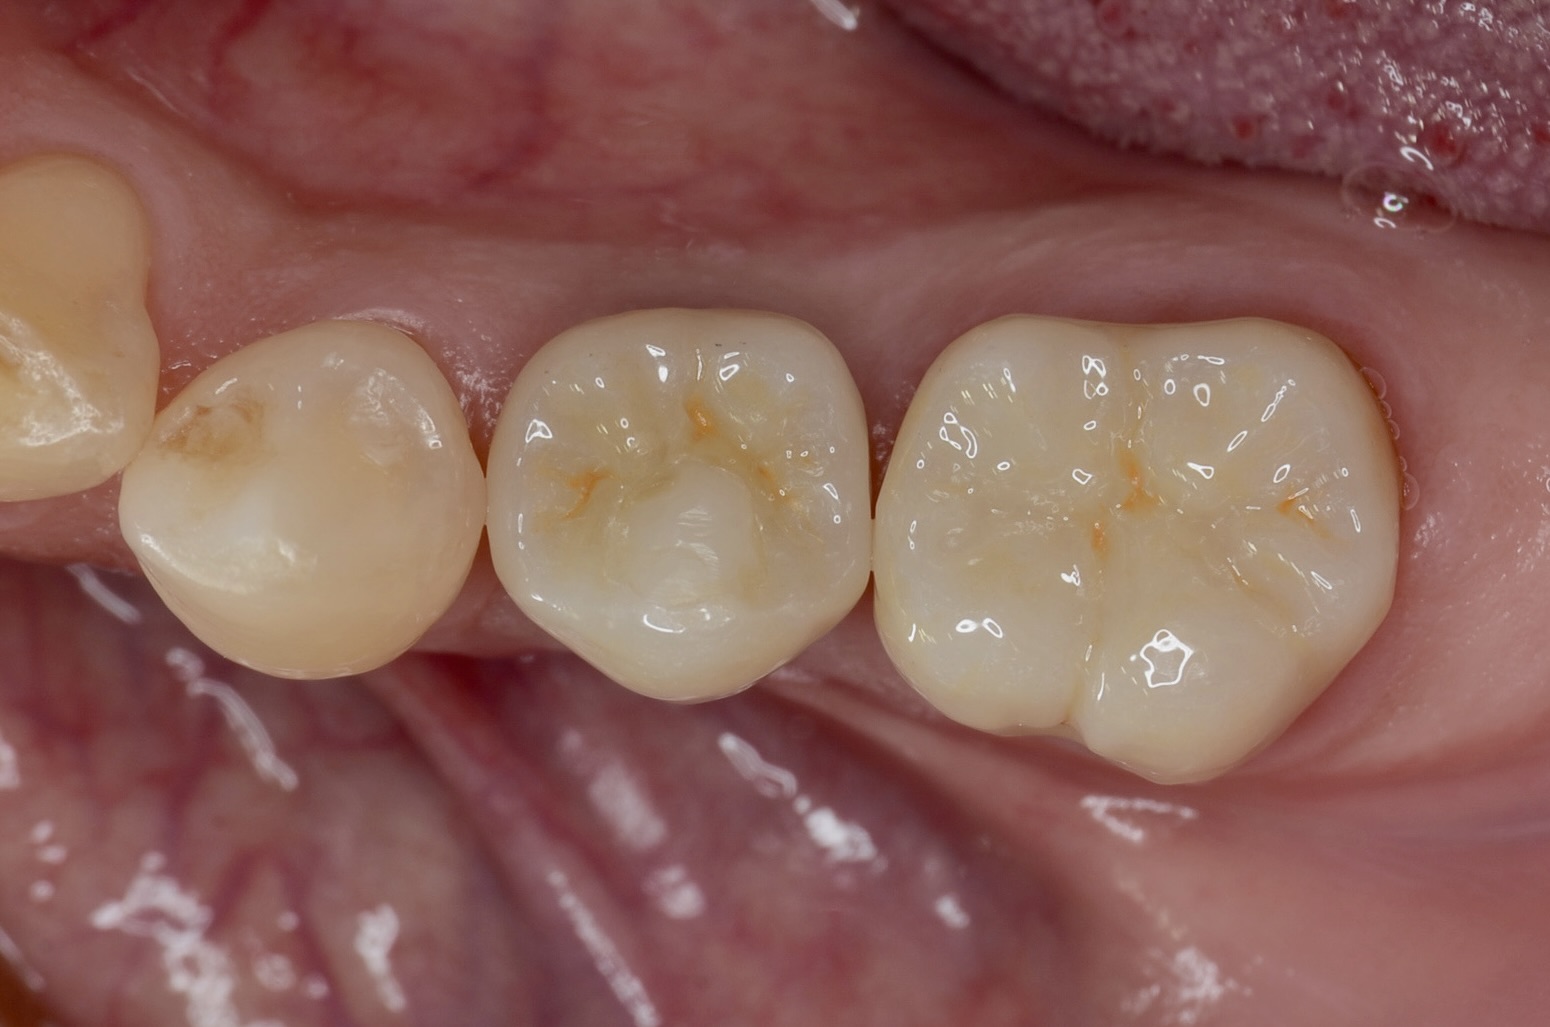

咬合面観

インプラントのアクセスホールをレジンで埋めて、7番にジルコニアクラウンが入りました。 -